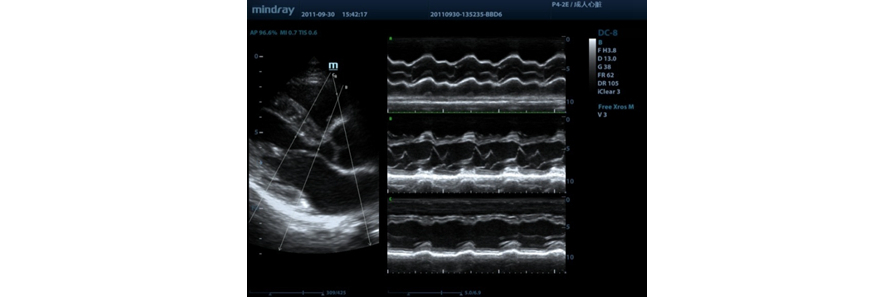

Free Xros M?

?rnek hatlar?n? her hangi bir a??ya ?zgĂŒrce yerle?tirerek kesin bir anatomik g?zlemin kazan?lmas?. 3 ?rnek hatt?n?n ayn? anda g?rĂŒntĂŒlenmesi sayesinde daha iyi g?rĂŒntĂŒlere ula??lmas?.